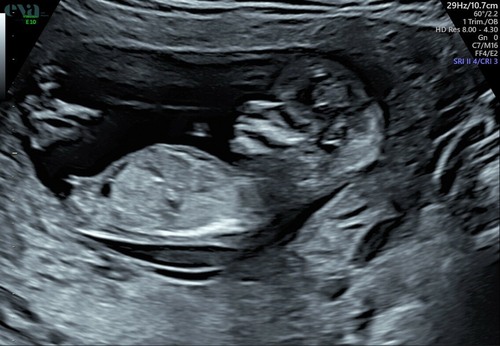

13+1 weken

Deze is gisteren gemaakt tijdens de 13 weken echo.

Ik ben super benieuwd 💗💙